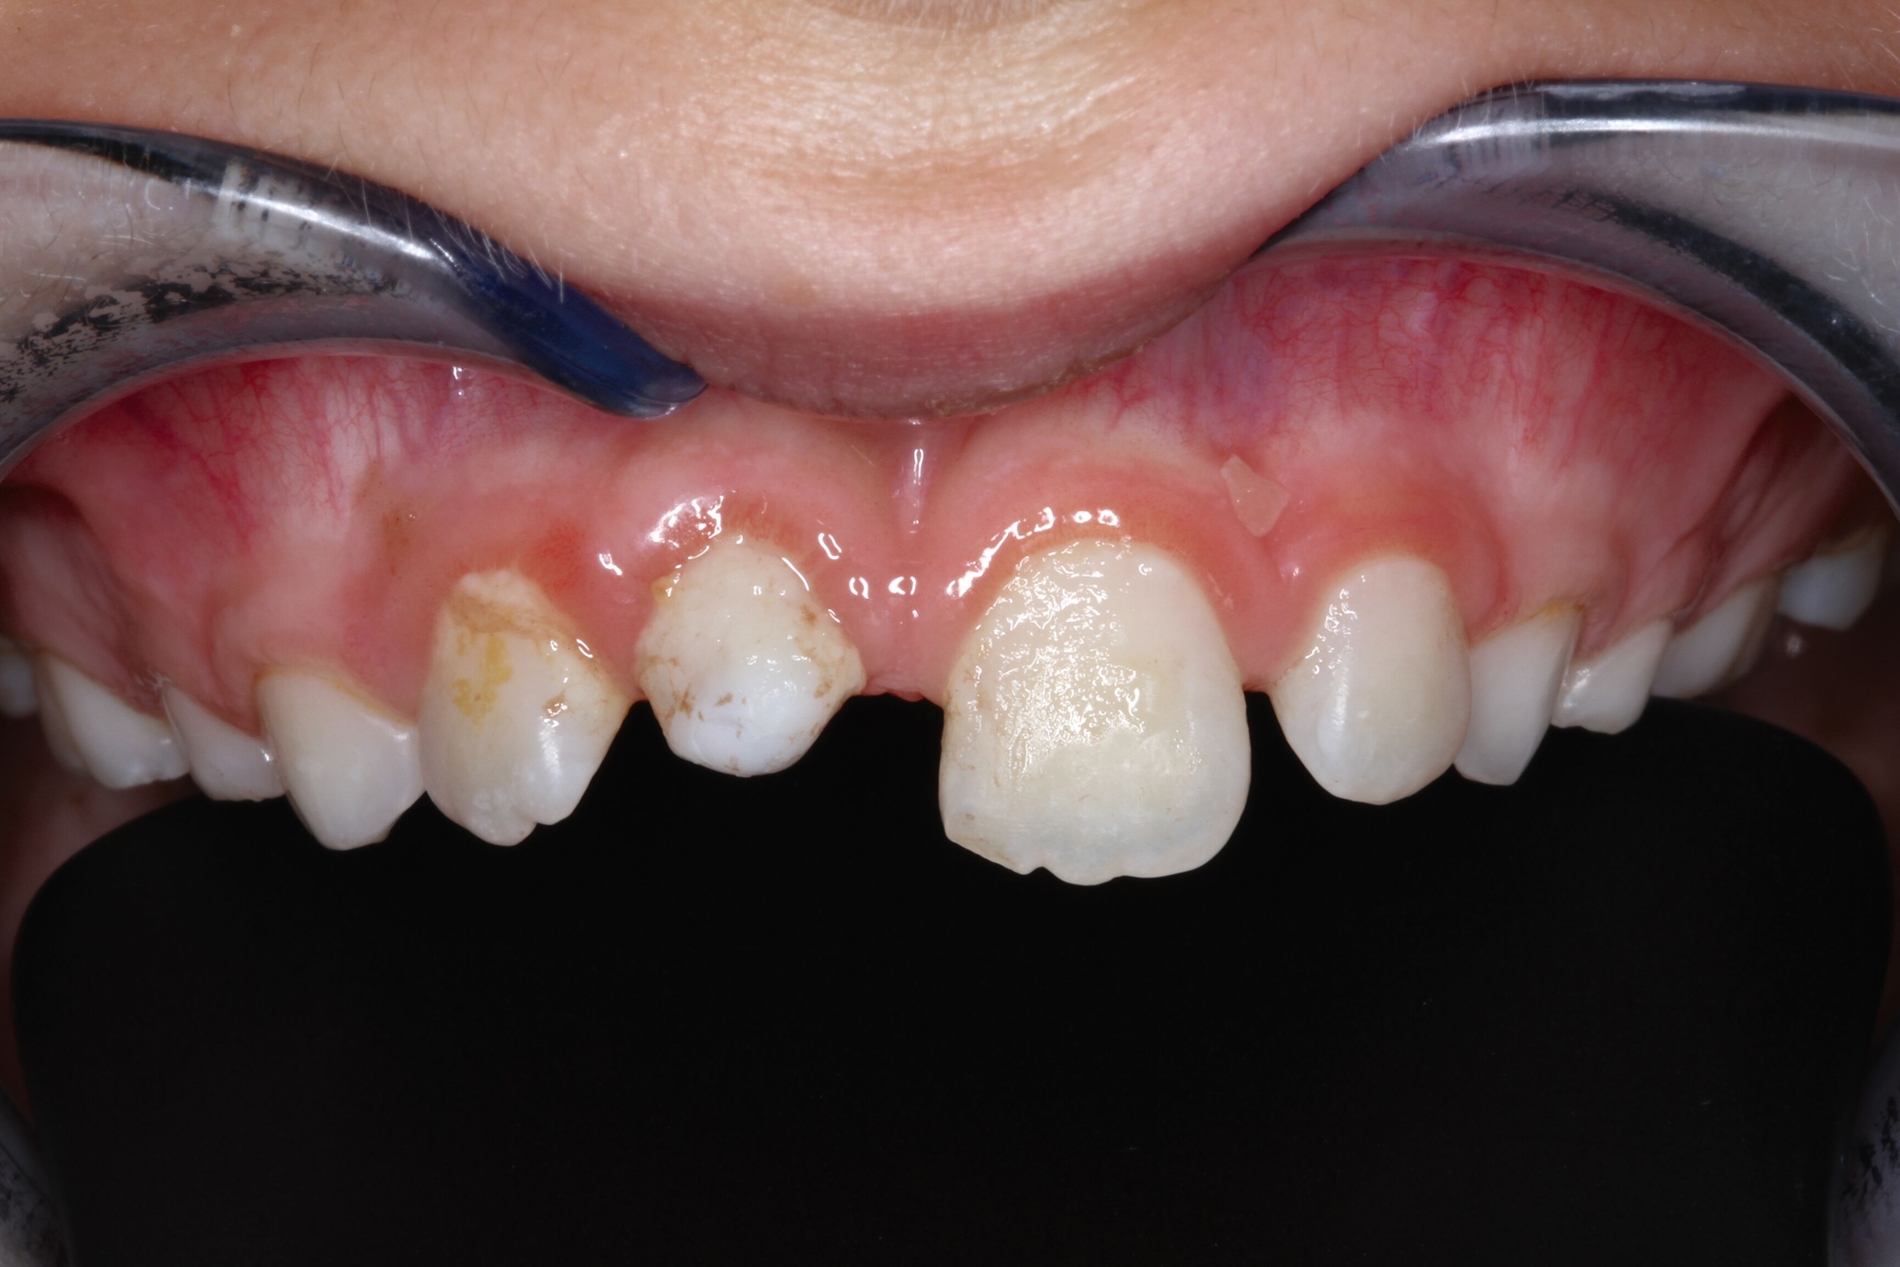

Aufgrund der infausten Prognose des replantierten Zahnes 11 entschieden wir uns für die Milchzahn-Transplantation von 83 nach 11, da dieser die längste Wurzellänge aller vier Milcheckzähne besaß. Im selben Eingriff wurde der replantierte Zahn 11 entfernt und der Milcheckzahn 83 in die Lücke 11 transplantiert. Das Transplantat wurde für drei Wochen mit einer Überknüpfnaht fixiert, die mit Kunststoff (Tetric EvoFlow®, Cavifil, Bleach XL) adhäsiv gesichert wurde (Abbildung 3a). Nach der Entfernung der Naht zeigte sich ein reizlos eingeheiltes Transplantat mit Lockerung I. Grades, negativem Perkussionstest sowie reizlosen gingivalen Verhältnissen bei einer Taschentiefe von 1 mm (Abbildung 3b).

Das Transplantat wurde acht Wochen später schrittweise in adhäsiver Technik mit Komposit aufgebaut (Abbildungen 4a und 4b) und blieb so für weitere 4,2 Jahre – funktionstüchtig – im Mund der Patientin, bis ins Alter von 13,2 Jahren. Die psychosozialen Folgen dieser sofortigen ästhetischen Rehabilitation können gerade bei Mädchen gar nicht hoch genug eingeschätzt werden.